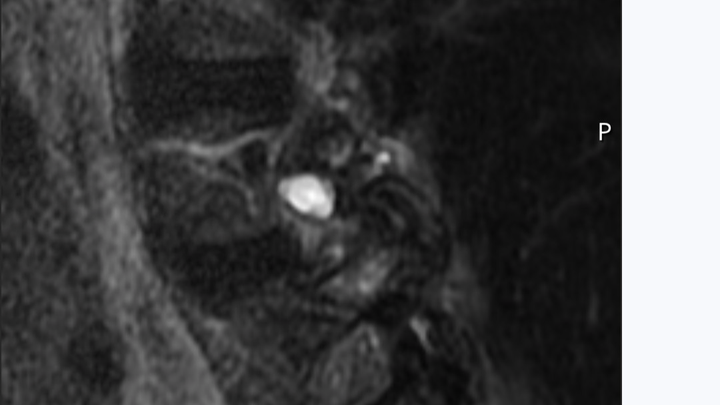

Here is the MRI of the growth from two views. As you can see it's right on the spine itself pushing on the nerves simulating a ruptured disk.

Surgery itself is relatively simple. He will cut through the back muscles and remove the growth as long as it has not grafted to the nerve root. He will remove bone to open the chamber where the root feeds the nerves to my right leg and hip.